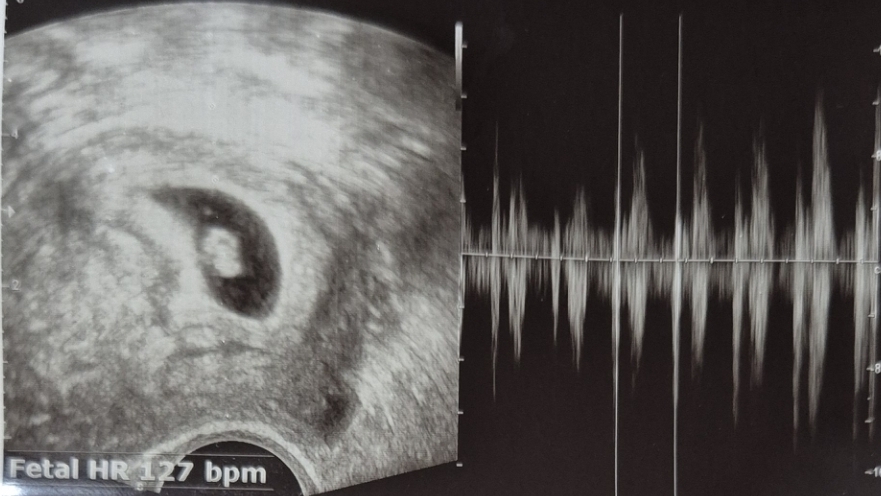

첫 심장소리 듣고왔어요

우리애기 첫 심장소리를 듣고왔어요! 오늘이 6주4일±4 였어요 몇일전에 붉은피가 묻어나 야간진료로 급하게 병원에 방문했어요. 이상은 없다고 했지만 그 뒤로 긴장도가 올라간 상태에 어제 천둥소리에 놀랐더니, 배도 쥐어짜듯 너무 아프길래 오늘 병원 방문했습니다. 피고임도 없고, 아이도 주수에 맞춰 잘 크고 있다고 설명해주시더니. 쿵쾅쿵쾅 애기심장소리가 들리는순간 그동안 걱정했던 마음이 녹아내리는 기분이 들었어요 ㅠㅠㅠㅠ.. 너무 다행이에요